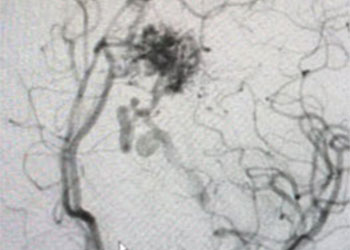

Endovascular:

Carotid Cavernous Fistula (CCF)

Author: Jonathan L. Brisman M.D., F.A.C.S., Read More!